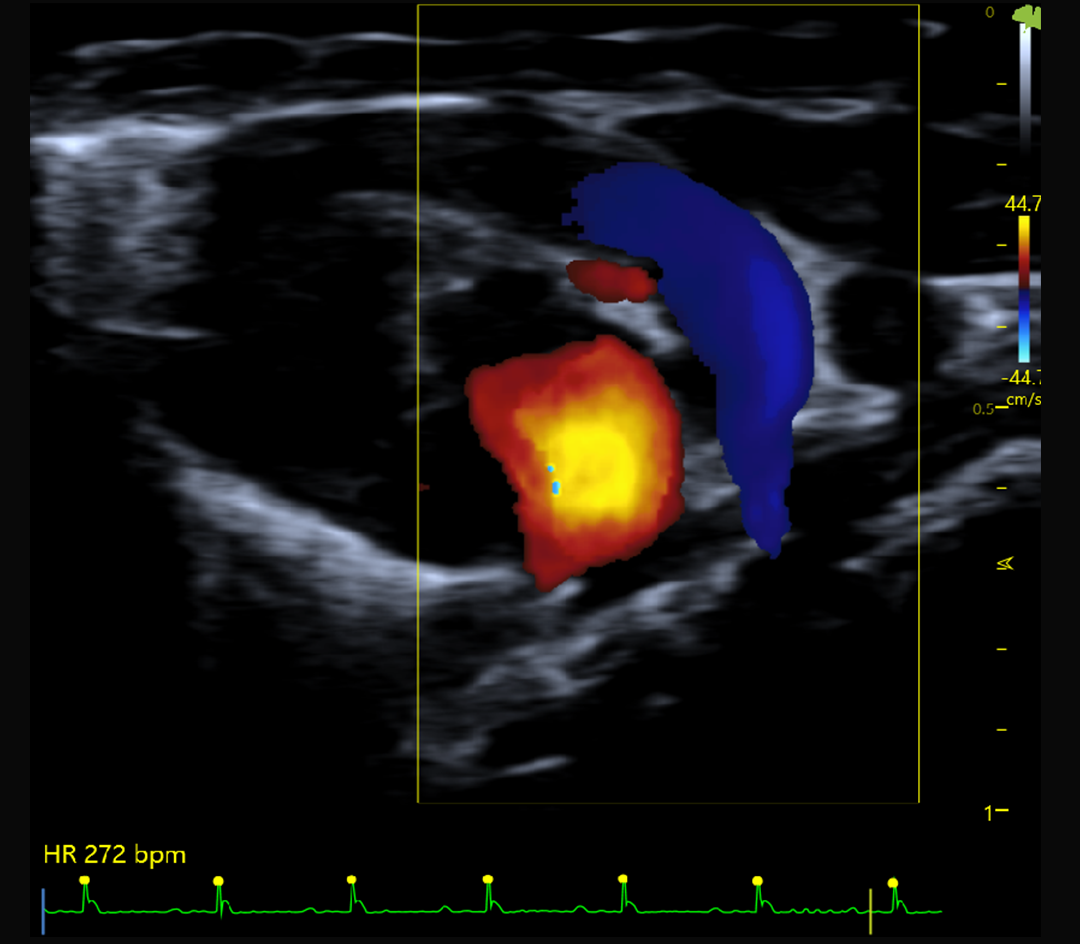

Fonction systolique et diastolique

Hémodynamique et flux sanguins

Imagerie cardiaque haute cadence chez la souris et le rat

Doppler couleur, pulsé et puissance

Le V6 LAB intègre des algorithmes dédiés au traitement massif des données RF :

Doppler couleur, Doppler pulsé et Doppler puissance

Résultat : une imagerie fine, stable et quantitative, adaptée à l’étude de la fonction cardiovasculaire, du flux sanguin et des structures tissulaires complexes.